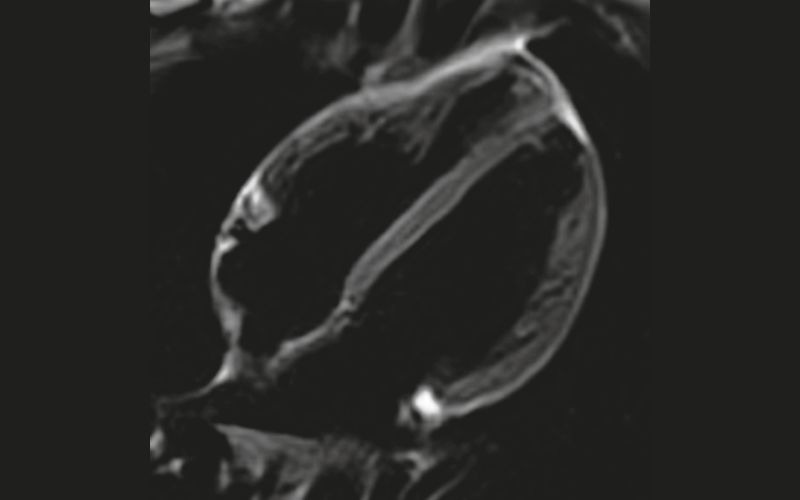

3T MRI offers better enhanced cardiac imaging when compared to 1.5T MRI. The improved resolution leads to a more accurate diagnosis and evaluation of various conditions such as heart failure, congenital heart disease and myocardial scarring. 3T MRI provides better myocardial perfusion imaging, delayed enhancement and blood flow assessment. The detailed images of the heart’s anatomy and function aid in the diagnosis of critical conditions.

The higher magnet strength of 3T MRI compared to 1.5T MRI allows for greater signal to noise ratio (SNR) which provides better detailed imaging. The improved SNR increases spatial or temporal resolution and decreases acquisition time of the scan sequences.